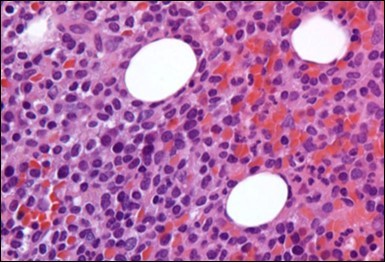

The leukaemia cells may enunciate a characteristic immune phenotype, crucial for a confirmatory diagnosis. The peripheral blood mononuclear B cell population may display a kappa or lambda light chain restriction. The phenotype of classic hairy cell leukaemia may be delineated by concurrent, immune reactive CD19+ CD20+,CD 11c+, CD25+, CD103+ and CD123+. An intensely immune reactive CD200+ and a non reactive CD27- antigen may be present2, 4. Evaluation of a trephine bone marrow biopsy and bone marrow aspirate may define the degree of tumour infiltration. A dry tap on account of prominent bone marrow fibrosis may be elucidated at preliminary diagnosis. A decline in the normal haematopoiesis may account for a hypo-cellular marrow in 10% instances. Gradation of cellular infiltrating of the leukaemia within the bone marrow may be appropriately investigated with immune –histochemical stains2, 4. Immune staining for CD20+, annexin 1 and VE1 (a BRAF V600E stain] may validate the diagnosis and precisely analyse the extent of malignant bone marrow infiltration[8]. Determination of BRAF V600E mutation may be critical in therapeutically non responsive individuals with applicable standard therapy or in instances of multitudinous reoccurrences[9]. Deploying inhibitors of BRAF V600E gene may be efficacious in patients impervious to approved therapy. The mutation necessitates a comprehensive scrutiny of the implicated individuals with a sensitive molecular assay which may discern up to < 10% of the hairy leukaemia cells appearing in the peripheral blood smears or bone marrow aspirates diluted with peripheral blood or aspirates elucidating a dry tap[2,4]. Allele specific polymerase chain reaction (PCR) or a next generation sequencing may be optimally employed to circumvent false negative outcomes. If the leukaemia cells are sparse or if particularly sensitive & efficacious molecular techniques are not accessible, the application of appropriate immune histochemical stains to the bone marrow biopsy such as a BRAF V600E mutation stain (VE1) may detect the hairy cells and conclusively diagnose the condition[2,4,10]. Figure 1, Figure 2, Figure 3, Figure 4, Figure 5, Figure 6, Figure 7, Figure 8, Figure 9, Figure 10, Figure 11, Figure 12, Figure 13, Figure 14.

Figure 1.HCL: hairy cells infiltrating designated spaces(17).

Figure 2.HCL: hairy cells with projecting cytoplasm abutting bony trabaculae(18).

Figure 3.HCL: hairy cells dispersed within the native architecture(19).

Figure 4.HCL: hairy cells with widely spaced nuclei(20).